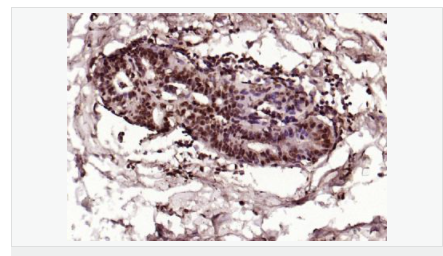

交叉反應(yīng):Human,Mouse,Rat(predicted:Dog,Pig,Rabbit,GuineaPig) 推薦應(yīng)用:IHC-P,IHC-F,ICC,IF,Flow-Cyt,ELISA

| 英文名稱 | phospho-HSP70 (Tyr611) |

| 中文名稱 | 磷酸化熱休克蛋白-70抗體 |

| 產(chǎn)品類型 | 磷酸化抗體 |

| 交叉反應(yīng) | Human, Mouse, Rat, (predicted: Dog, Pig, Rabbit, Guinea Pig, ) |

| 產(chǎn)品應(yīng)用 | ELISA=1:5000-10000 IHC-P=1:100-500 IHC-F=1:100-500 Flow-Cyt=1μg/Test ICC=1:100 IF=1:100-500 (石蠟切片需做抗原修復(fù)) not yet tested in other applications. optimal dilutions/concentrations should be determined by the end user. |

| 免 疫 原 | KLH conjugated Synthesised phosphopeptide derived from human HSP70 around the phosphorylation site of Tyr41:GL(p-Y)QG |